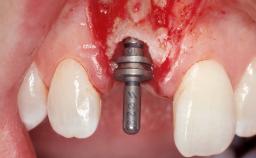

A 30-year-old female patient had lost tooth 21 and was referred to our clinic for consultation and treatment. Due to advanced apical infection, tooth 21 had been extracted two months earlier at another clinic and an acrylic-resin tooth had been bonded to the adjacent teeth. The patient desired implant treatment to avoid any damage to the adjacent natural teeth. While the patient had no history of any systemic disorder, she was a heavy smoker and exhibited medium to advanced periodontitis in the entire jaw. After the initial treatment to achieve a pocket probing depth of less than 4 mm and no bleeding on probing, a decrease in the height of the papillae mesial and distal to the extraction site and overall gingival recession were observed.

| Type of Implants | One-Piece|Reduced-Diameter |

| Abutment Type | CAD/CAM |

| Prosthesis Type | FDP |